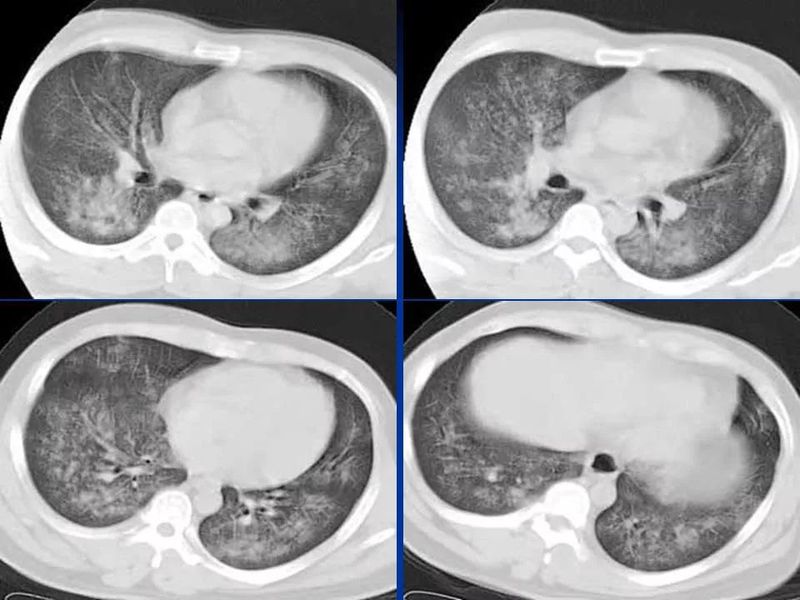

主任提醒:这个病很容易误诊为肺炎!